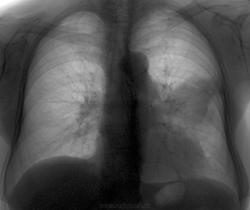

Бабушка из села, о такой штуке, как флюорография - "слыхом не слыхала", жалоб нет.

Похоже на плевральные дела,да вот средостение не влево ли уехало.Без бокового не написать заключение.

Так хотел небольшой интриги, что безвозвратно удалил боковой. Уж очень похоже на междолевой плеврит, если б слева была междолевая плевра. А так... В общем завтра будет боковой и т.д.

Мы ждём.А в головке левого корня "круглит".

Так это рак

Небольшой отчет о проделанной работе. Перед боковой прозвучала жалоба на боли в левой половине грудной клетки и я подумал о плеврите. Но после боковой надежды на плеврит не оправдались. Направил в онко на КТ. К сожалению картинок выставить не могу. Но по заключению - тумор, деструкция ребра (оттуда и боль), мета в л/узлы средостения и правое легкое.

Без дайкома нового не добавлю, не всё старое видно. Опухоль есть, мета в лимфоузлы есть.